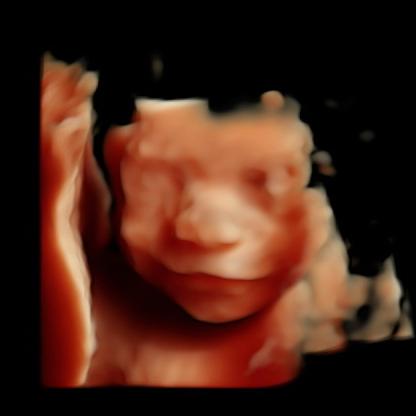

Quaid

Baby

My Love πŸ˜πŸ˜πŸ˜πŸ€°πŸ½πŸ‘©πŸ½β€πŸΌπŸ‘ΆπŸ½